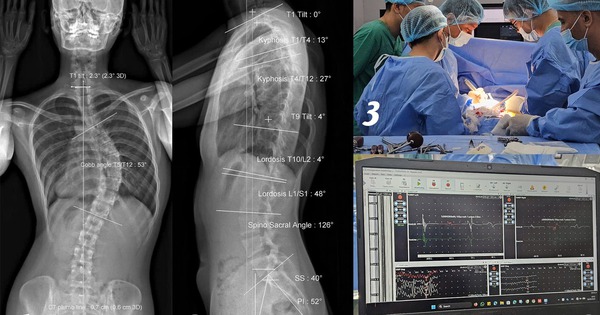

Cô gái soi gương thấy lưng có dấu hiệu lạ, không ngờ cột sống đã cong 53 độ

(NLĐO) - Trong 1 lần soi gương thấy dáng lưng có dấu hiệu bất thường, đến khi đi khám, cô gái 18 tuổi sốc khi biết bị vẹo cột sống ngực 53 độ.